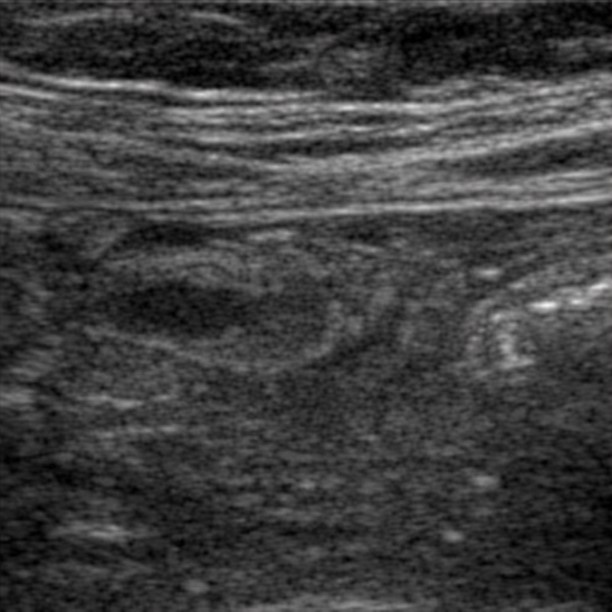

[362,Gastrointestinal [GI]] 40/F,Right lower quadrant pain

Gastrointestinal [GI]

US,

What is the most likely diagnosis?

Acute appendicitis

Cecal diverticulitis

Epiploic appendagitis

Omental infarction

Crohn disease